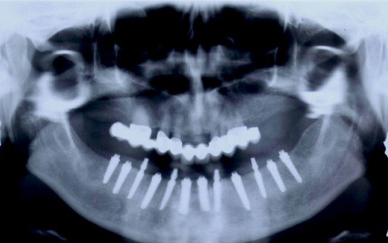

Částečně ozubená čelist

V případě chybění většího počtu zubů v postranních úsecích čelistí je možné ošetření pomocí implantátů, které nahradí ošetření pomocí snímacích náhrad kotvených na zbývajících zubech nebo patře.

Podmínkou je opět dostatečné množství kosti.

Protetické řešení může být pomocí můstku, který je kotvený na implantátech nebo pomocí jednotlivých korunek na implantátech.

V zásadě je možné do těchto můstků zařadit i přirozené zuby, zejména pokud je potřeba tyto zuby ošetřit proteticky – korunkami. Korunky nebo můstky mohou být na implantáty nacementovány nebo přišroubovány.

Zdravé zuby zůstanou zachovány a přitom náhrady jsou pevné, jako na vlastních zubech